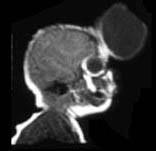

问题 根据MRI表现,考虑何种疾病是 ( )

选项 A、大脑导水管狭窄 B、脑彭出 C、Arnold-Chiari畸形 D、颅底凹陷症 E、Dandy-Walker综合征

答案 B